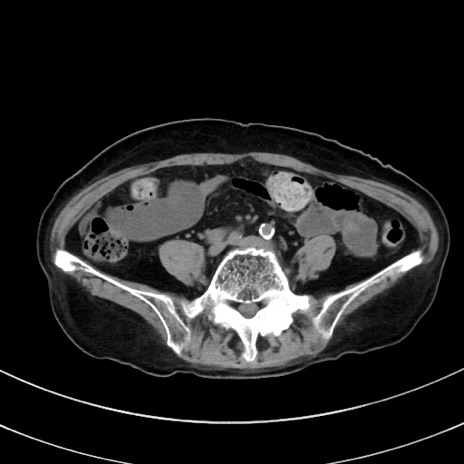

症例33(横断像)

【症例】70歳代 女性

【主訴】心窩部痛

【現病歴】延髄病変の精査・加療にて神経内科入院中。本日より心窩部痛あり。

【既往歴】虫垂炎

【身体所見】右下腹部を中心に圧痛と反跳痛あり。

【データ】WBC 10900、CRP 0.02